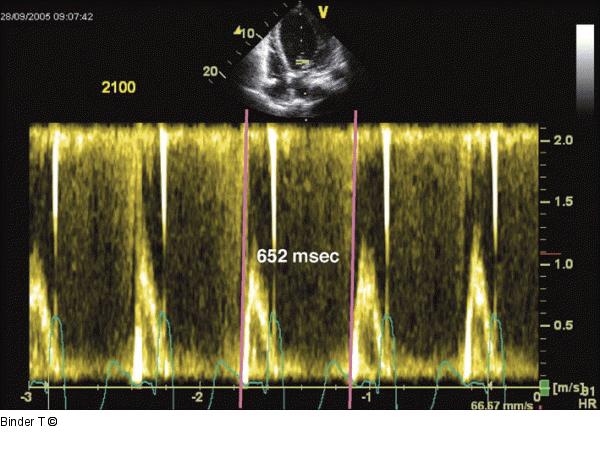

Abbildung 13: Bestimmung der Zykluslänge PW-Dopplerspektrum des Mitraleinstroms: Bestimmung der Zykluslänge (z. B. Beginn der E-Welle bis zum Beginn der nächsten E-Welle). Diese Beträgt 652 msec (entspricht einer Herzfrequenz von 81/min). Dieser Meßwerte dient der Bestimmung der prozentuellen Dauer der Diastole bezogen auf den gesamten Herzzyklus. |

Abbildung 13: Bestimmung der Zykluslänge